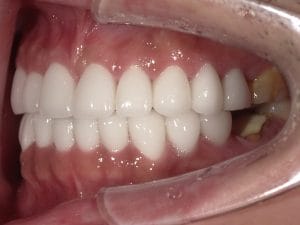

Case030

他院で実施したセラミック矯正の再治療を希望された患者様の症例です。

■色をもっと透明感のある白にしたい。

→当院自慢の一流技工士による最高品質ジルコニアセラミックにて透明感のある白へ

実際は写真でみるよりももっと透明感があります。

■前歯の歯の長さが違うのを治したい

→レーザーによる歯肉整形術で均等な歯の長さへ

■出っ歯に作られている前歯を引っ込めたい

→施術を担当した理事長の形成により、内側に入れるデザインにして洗練された口元へ。これによりEラインも整います。

■歪んだ歯並びを綺麗に

→施術を担当した理事長による形成、印象と技工士との連携により綺麗な歯並びへ

■タバコを吸ってた頃のヤニのついた黒くなってしまった歯茎が気になる

→レーザーによるメラニン色素除去でピンク色の歯茎に戻して若々しい印象へ